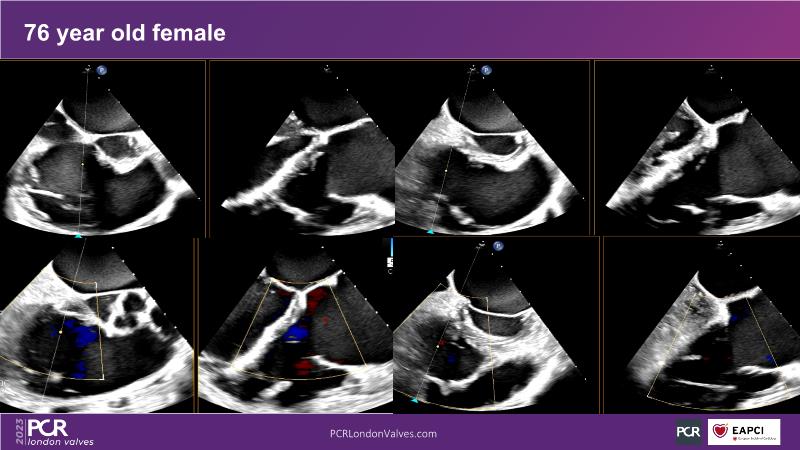

This session explores the features of the PASCAL Precision and the EVOQUE tricuspid replacement systems through simulators and case presentations, while a panel of experts discuss the technology, witnessing live demonstrations of treating mitral and tricuspid regurgitation patients.

- To learn about the differentiating features of the PASCAL Precision system showcased in a series of simulators alongside case presentations

- To interact with a panel of experts discussing the PASCAL Precision system technology and showcasing, live, its different key features in action and how they help treat mitral regurgitation and tricuspid regurgitation patients